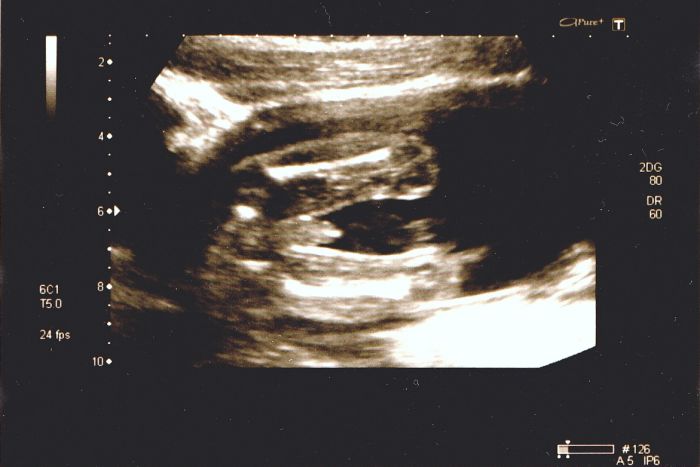

ahojky, tak máme po velkém UZ, kde bylo všechno v pořádku. Vyšetření nám trvalo skorominut, protože se prcek pěkně vrtal a přetáčel se a nech zůstat chvilku vklidu :D doktorům dal pěkně zabrat :D jinak nám na 100% potvrdili kluka, tak to bude Daniel :) dědečkové a tatínek se velmi těší :D